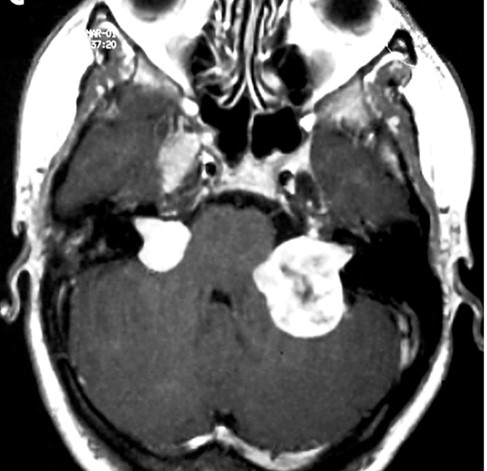

양측 청신경종양을 가진 2형 신경섬유종의 대표 뇌 MRI(자기공명영상)

2형 신경섬유종증의 대표적인 병인 ‘양측 청신경종양’은 종양이 커지면 양측 청각 장애를 가져오고, 다른 뇌신경 및 척수에 종양이 성장하면 뇌신경장애 및 상-하지 마비 등을 초래한다.